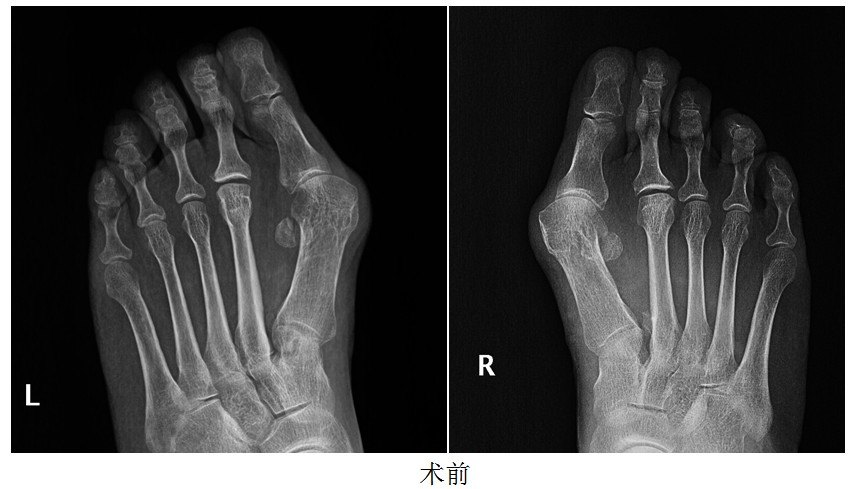

骨六科重度拇外翻并第2趾交叉趾畸形的治疗

图片尺寸2673x2191